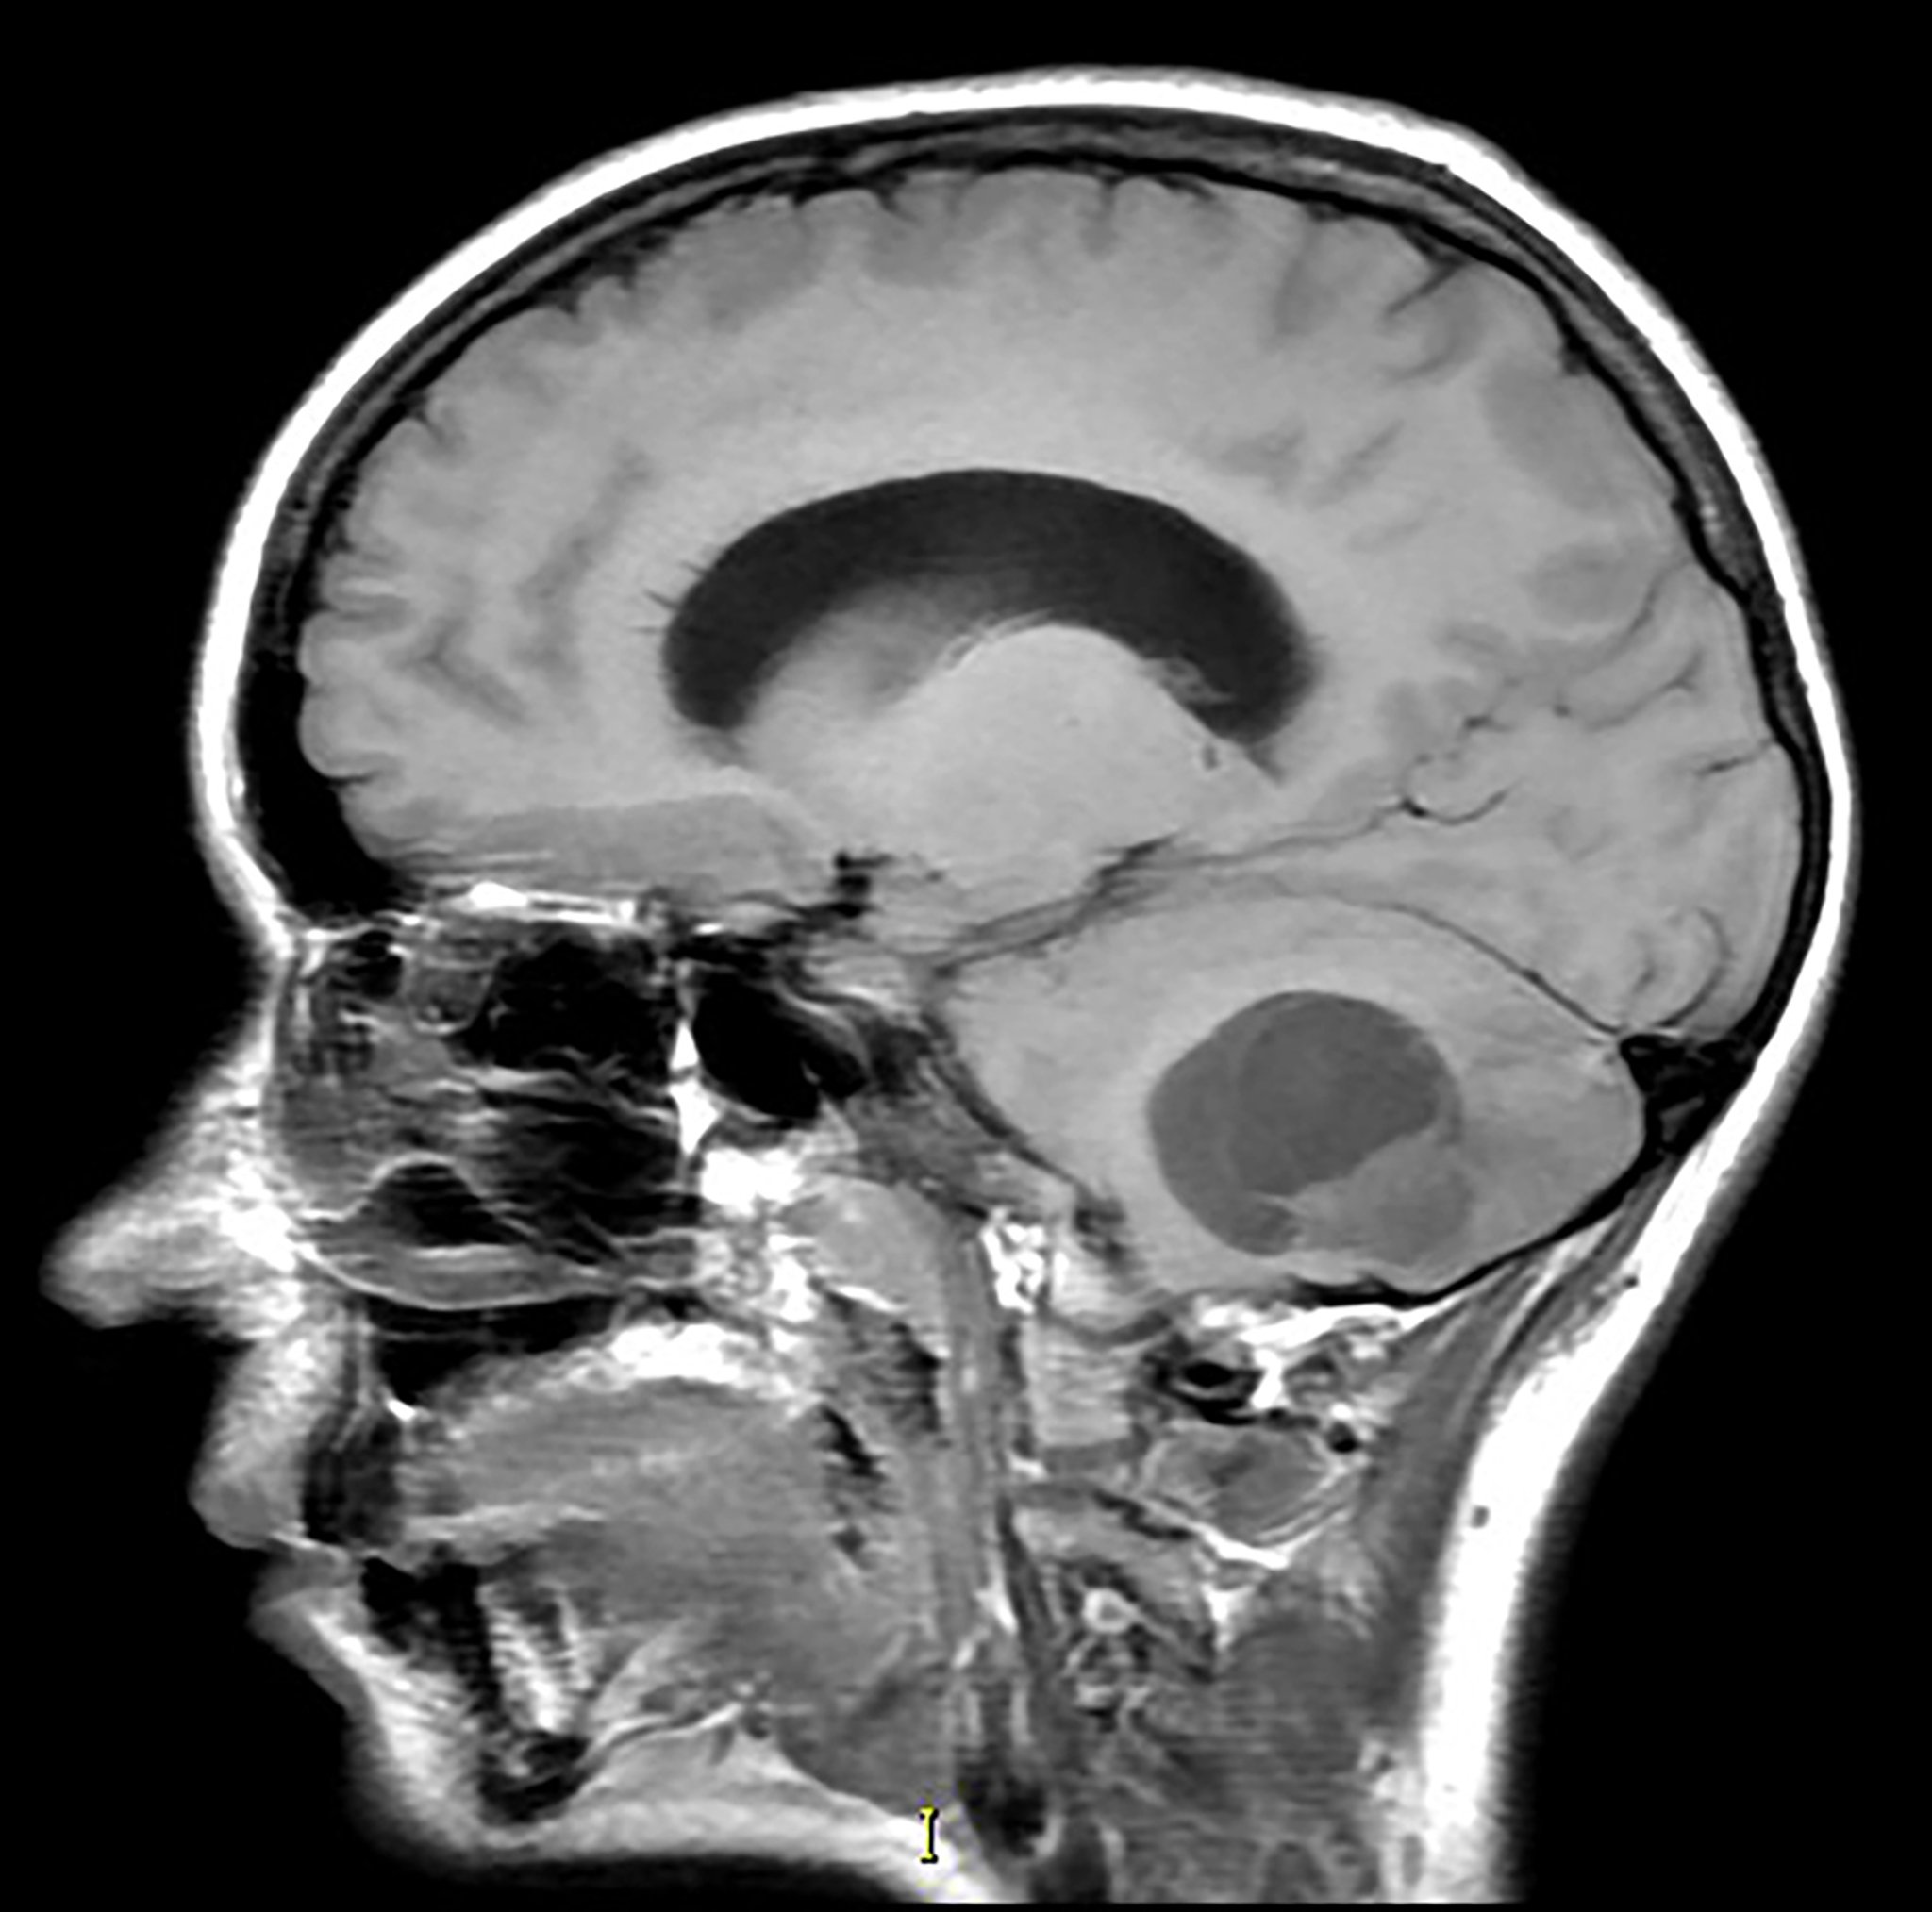

Hemangioblastomas cerebelosos

Esta imagen de resonancia magnética sagital potenciada en T1 sin contraste muestra una masa parcialmente quística y sólida en el cerebelo inferior con efecto de masa asociado. Este es el aspecto más común de un hemangioblastoma. Este tumor se observa con mayor frecuencia en pacientes con síndrome de von Hippel-Lindau.